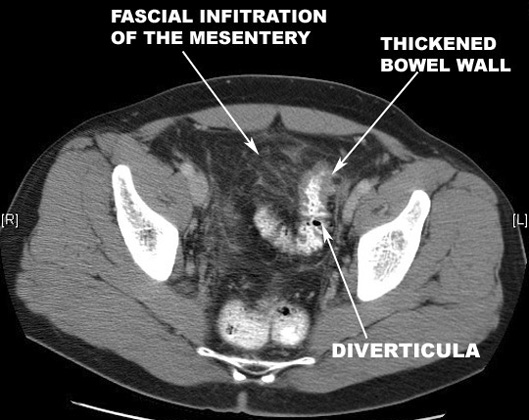

What are the imaging findings of diverticulitis?

Diverticulitis